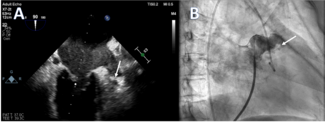

- A Contemporary Algorithm to Guide Percutaneous Coronary Intervention in High-Risk Spontaneous Coronary Artery Dissection

Spontaneous coronary artery dissection (SCAD) is increasingly common, and while most cases are managed conservatively, some demand urgent intervention. This

article breaks down a clear, step-by-step approach for high-risk SCAD, including practical tips on wiring, intravascular ultrasound use, and cutting-balloon strategies to safely restore flow. A must-read for cardiologists facing this challenging percutaneous coronary intervention scenario.